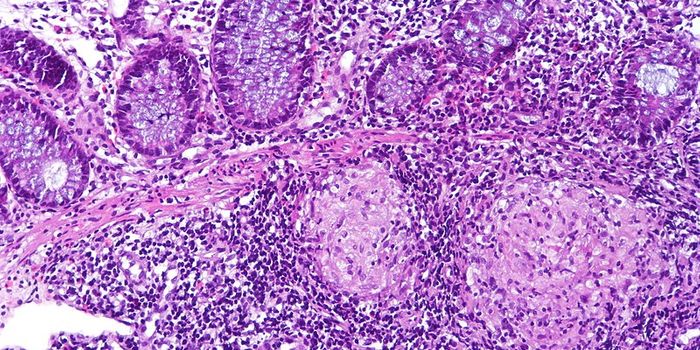

![Anti-PRAME antibody [EPR20330]](https://d3bkbkx82g74b8.cloudfront.net/eyJidWNrZXQiOiJsYWJyb290cy1pbWFnZXMiLCJrZXkiOiJjb21wYW55X3Byb2R1Y3RfcHJvZmlsZV9pbWFnZV9mMzEwNTY4MGY1NmVmZjU3ZjZhMWRkZTU2M2Q4YjBmODZjMDJkNDE4XzMwMDA3MTg1ODEyLmpwZyIsImVkaXRzIjp7InRvRm9ybWF0IjoianBnIiwicmVzaXplIjp7IndpZHRoIjozMDAsImhlaWdodCI6MzAwLCJmaXQiOiJjb3ZlciIsInBvc2l0aW9uIjoiY2VudGVyIiwiYmFja2dyb3VuZCI6IiNmZmYifSwiZmxhdHRlbiI6eyJiYWNrZ3JvdW5kIjoiI2ZmZiJ9fX0=)